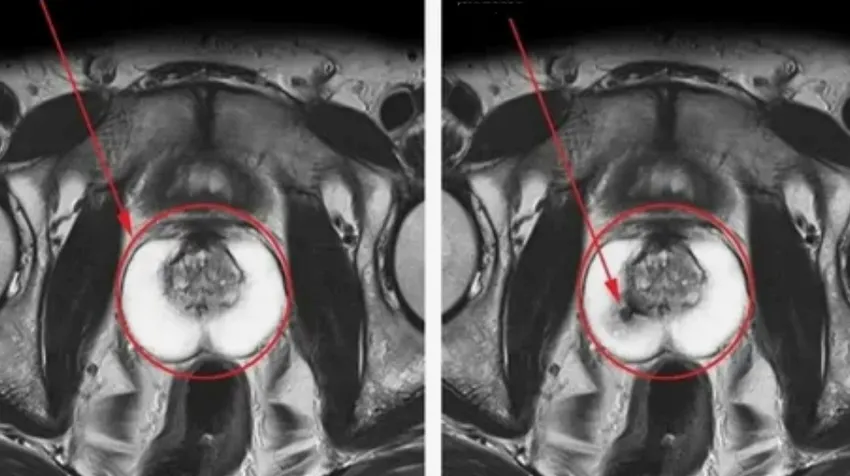

Aparecen células cancerosas

Debido a que la glándula está constantemente inflamada, en ella aparecen y crecen células cancerosas. Esto lleva primero al adenoma de próstata, y luego al cáncer. El cáncer de próstata es incurable. Normalmente se detecta solo en fase terminal. Y a los hombres solo les quedan unos meses de vida. El cáncer de próstata se considera el tipo de oncología más peligroso y vergonzoso.

Así se ve el cáncer de próstata.